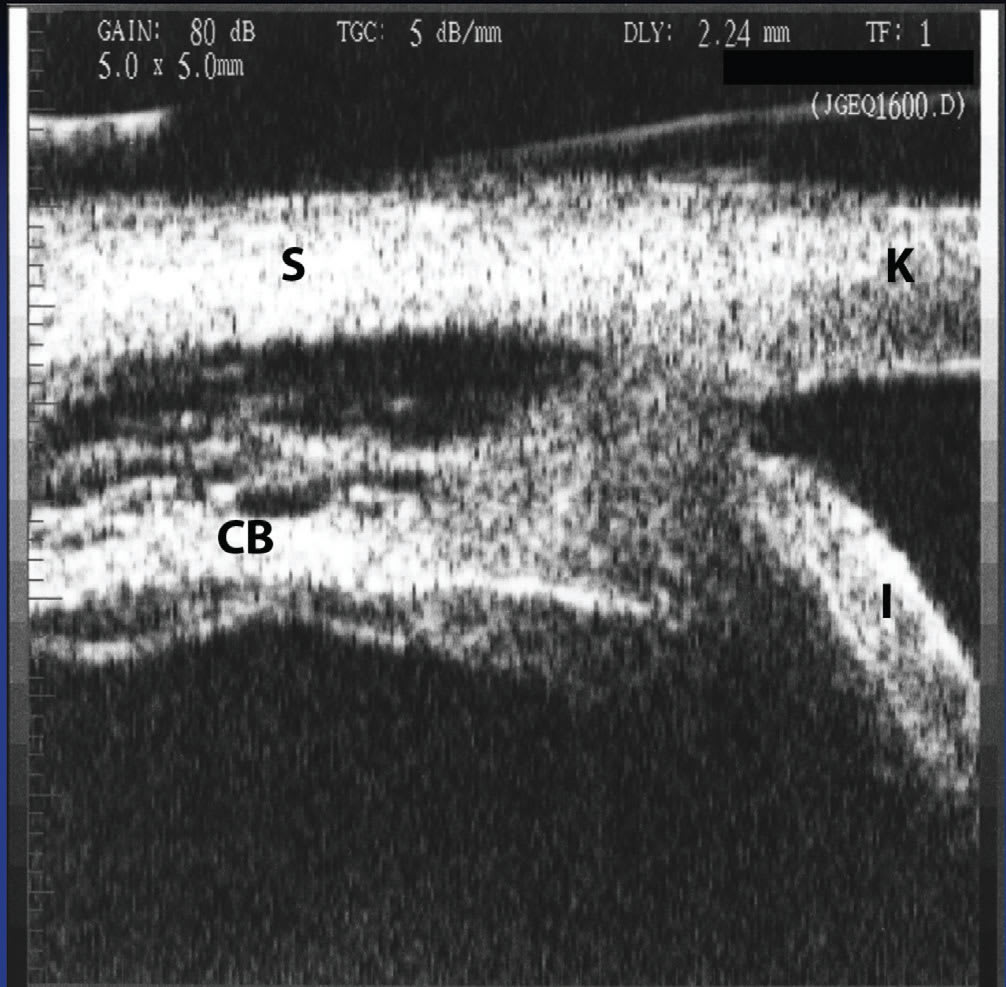

▪ B-scan ultrasonography. B-scan ultrasonography has been most useful in the evaluation of intraocular disorders associated with opacified media. Opacified media can be caused by intraocular inflammation and its complications, as well as other conditions, including but not limited to corneal opacification, anterior chamber hyphema or hypopyon, posterior synechiae with miosis, cataract, vitreous hemorrhage, and retinal detachment. Ultrasound can also be used to evaluate inflammatory infiltration of the choroid, as occurs in chronic uveitis including Vogt-Koyanagi-Harada (VKH) syndrome, sympathetic ophthalmia, and combined scleral and choroidal thickening from scleritis.39 In these situations, ultrasound becomes useful in evaluating patients prior to instituting therapy or planning surgery. In the presence of clear media, high-frequency ultrasound or ultrasound biomicroscopy (UBM) can be of additional use, particularly for examination of the region of the ciliary body and pars plana, which are often involved in patients with intermediate uveitis and can be difficult to visualize clinically (Figure 5).40 UBM may also identify occult foreign bodies in cases of chronic uveitis occurring after trauma.

Figure 5. Inflammatory ciliary body effusion and detachment detected on ultrasound biomicroscopy (UBM) in a patient with sarcoidosis with hypotony. S=sclera, K=cornea, CB=ciliary body, I=iris.